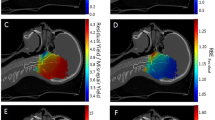

Figure 4 shows the iso-fluence contours at the centre slice of the metastatic lesion (see Fig. 2) for both the 690 nm and 565 nm treatments. The yellow contour shows the necrotic threshold dose of the spinal cord (0.02 J mm\(^{-2}\)), while the orange contour indicates the necrotic threshold for the metastasis (0.4 J mm\(^{-2}\)). For the 690 nm treatment, the overall energy needed is estimated to be 1247.6 J. However, the potential overall damage to the spinal cord was around 4.7 cm\(^3\), which is almost the entire segmented spinal cord tissue. The 565 nm treatment shows significantly reduced damage to the spinal cord (2.4 cm\(^3\), representing \({\sim }\,50\%\) damage reduction). However, the estimated required energy for the 565 nm treatment is infeasible at 167.3 kJ. Figure 3 compares the spinal cord dose-volume histograms of the two treatments. While the 565 nm wavelength can significantly reduce the damage to the spinal cord, it would require a much longer treatment duration.

Simulations for cylindrical diffusers light delivery

Similar to the cut-end fibres configurations, Fig. 5 shows the iso-fluence contours for a 2-cylindrical diffusers scenario at the two wavelengths. A similar trend is seen in that the 565 nm treatment significantly decreases the damage to the spinal cord. The damage reduction is more substantial than in the cut-end fibres scenario; the 565 nm wavelength yields a damage volume of only 1.4 cm\(^3\) (70% damage reduction). However, the required energy (9.3 \(\times 10^3\) kJ) would necessitate a much longer treatment duration.

Optimized treatment plans for wavelengths of (a) 690 nm and (b) 565 nm using a 4-source configuration (4 cut-end fibres with \(NA =0.22\) and \(200~\upmu\)m radius positioned at the center of the metastatic lesion). The resulting iso-fluence contours are overlaid on the 3D model, demonstrating the achievement of the minimum necrotic threshold within the metastatic region (0.4 J mm\(^{-2}\)) as per the colour map shown. The total energy at the 690 nm wavelength (\(E_{total}\) = 1247.6 J) was distributed across the 4 cut-end fibres [ordered horizontally from top left to bottom right) as follows: \(E_1=439.6\) J, \(E_2=487.6\) J, \(E_3=189.6\) J, \(E_4=130.8\) J. At 565 nm, the total energy \(E_{total}\) = 167.3 \(\times 10^3\) J, distributed across the 4 cut-end fibres as: \(E_1={64.6}\times 10^3\) J, \(E_2={49.5}\times 10^3\) J, \(E_3={32.4}\times 10^3\) J, \(E_4={20.8}\times 10^3\) J.

Optimized treatment plans for wavelengths of (a) 690 nm and (b) 565 nm using a 2-source configuration (2 cylindrical diffusers with a radius of 500 \(\upmu\)m). The resulting iso-fluence contours are overlaid on the 3D model, highlighting the the minimum necrotic threshold within the metastatic region (0.4 J mm\(^{-2}\)) as per the colour map shown. The total energy at the 690 nm wavelength (\(E_{total} = 2914\) J) was distributed across the 2 light-emitting cylinders as: \(E_1=1981.8\) J and \(E_2=932.4\) J, for the left and right sources respectively. At 565 nm, the total energy was \(E_{total} = {9.3}\times 10^6\) J, distributed as: \(E_1={8.35}\times 10^6\) J and \(E_2={0.95}\times 10^6\) J.